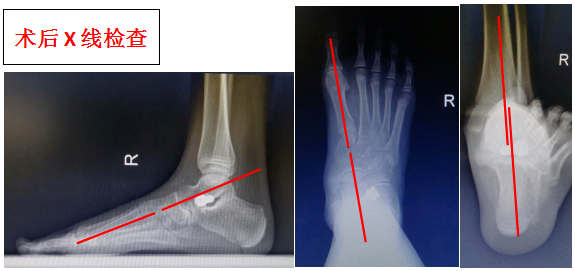

手術前后的影像學改變

【典型案例】左側青少年扁平足,1cm小切口即可解決!